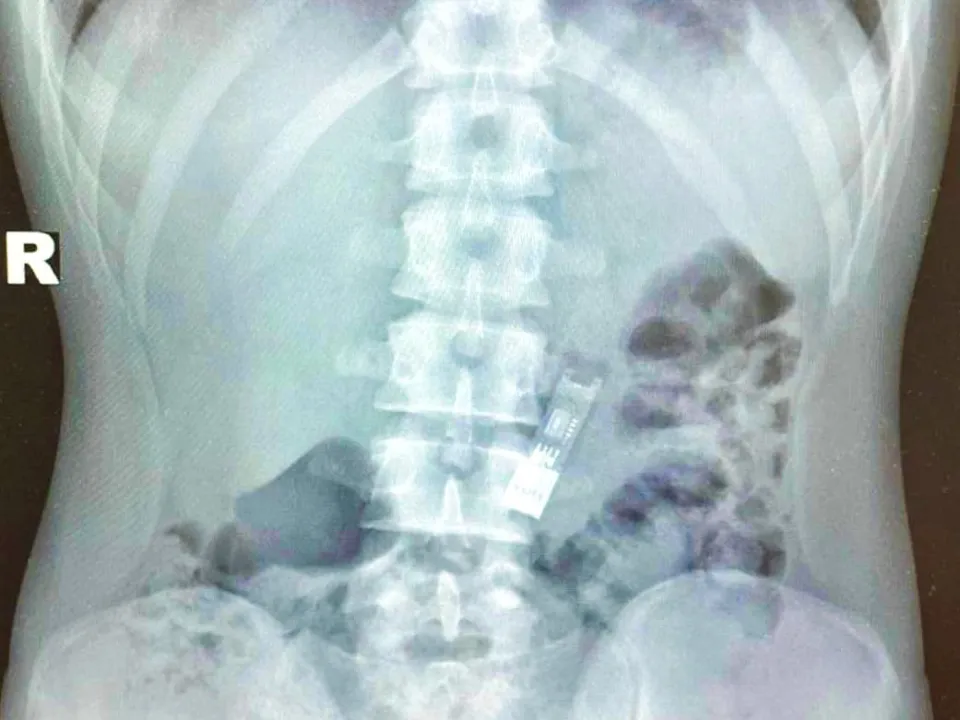

«При поступлении мы провели мальчику рентгенографию, которая показала, что флешка находится в желудке. В условиях операционной мы провели мальчику наркоз и подготовили его к операции. С помощью специальных эндоскопических щипцов без единого разеза извлекли флешку из желудка», — сказала лечащий врач-эндоскопист Дарья Степаненко.